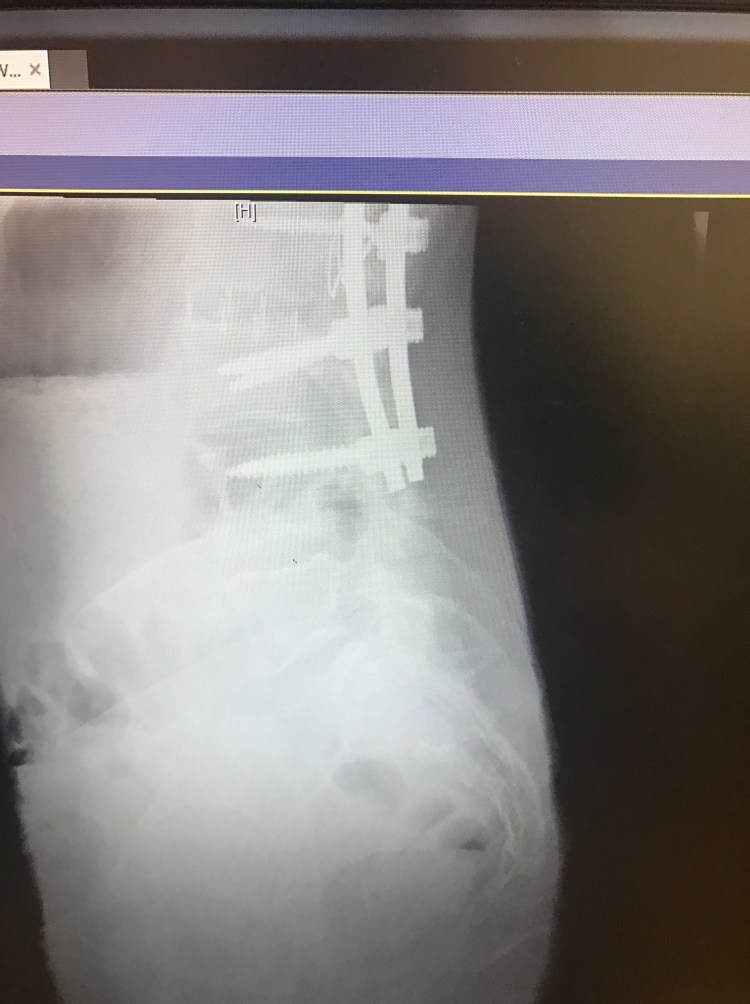

Last week, on Will’s birthday, it was also my 5 month post op appointment. I had a long list of questions and concerns and I was extremely anxious. These appointments always make me nervous and give me anxiety. While in the car on the long drive there, I can’t help but think about everything that happened and how it is going to affect me for the rest of my life. The feeling of these long rods screwed into my spine will never go away although hopefully get easier to forget about over time. I will never be able to bend my back or twist or bend side to side EVER. I still get asked this on a daily basis. The answer is never. Then, I have to continue to be cautious and not slip or fall or do anything that could cause a screw or rod to break and hope upon hope that these rods and screws can last the duration of my life without needing to be replaced. I already know somewhere in the future I will need another surgery to fuse the last few levels to my pelvis and boy am I already dreading for that day to come. Sorry to be a Debbie Downer. I guess it’s hard when people think because I am back at work, or can drive Will to preschool or wrap some damn Christmas presents that I must be “better”. Anyways…..my Doctor said that my bones are fusing. One side is fusing better than the other, but she is hopeful that the other side will catch up. She thinks that the first few months and all the added stress on my body prohibited me from really recovering until just recently. Fusions also can take up to 2 years from surgery to heal completely. All my screws are in place as well. We agreed I need to continue with physical therapy. Last week, I began light core muscle exercises with some resistance to help build my stomach muscles back up. Right now, I am having trouble standing up all the way do to the tightness in my hips and hamstrings. When I am not standing straight, it causes my back muscles to fire up causing some pretty crappy back pain. There’s still a long way to go to get this leg working and my shoulder is still causing me trouble as well. I am also still having blackout and dizzy spells which we had attributed to medicine, however, since being off everything for the most part, I am still having these multiple times a day. I was told I need to see a neurologist and get a primary doctor to run some tests.

You look great. Your xrays look even straighter now!!! Do you live in Cali? Im trying to figure that one out because your dressed like its cold and i thought you lived in Cali. Who was your surgeon again.? God Bless. Your a strong woman and sounds like you have a great supportive husband.

Yes in Northern California. Our weather can be in the 100’s in summer and in the 30’s in Winter. My back is actually a little less straight than right after with settling, but definitely staying put and starting to fuse!